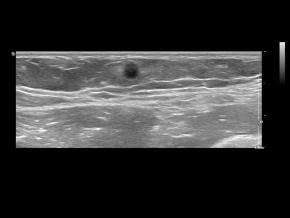

Elastography for the differential diagnosis of malignant versus benign testicular lesions: a meta-analysis

Ziwei Lin, Rui Lin, Huaiyu Wu, Linghu Wu, Jieying Zeng, Jinfeng Xu, Fajin Dong